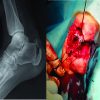

The patient was in a supine position with a pillow under her right buttock. Landmarks structures were identified with palpation: lateral malleolus, CCJ, and 5th metatarsal base. An antibiotic prophylaxis with 2 g of cefazoline was given. We used a thigh tourniquet inflated at 300 mmHg. First, we performed a 5 cm straight incision perpendicular to the CCJ. The peroneus longus and brevis tendons were identified. There was a cracking of the distal portion of the short fibular tendon. The two tendons were reclined in a posteroinferior position. Instability of the CCJ was confirmed with supination, inversion, and plantar flexion of the foot. There was a complete section of the dorsolateral calcaneocuboid ligament and a partial section of the bifurcate ligament. There was not any sign of cartilage injury (Fig. 6).